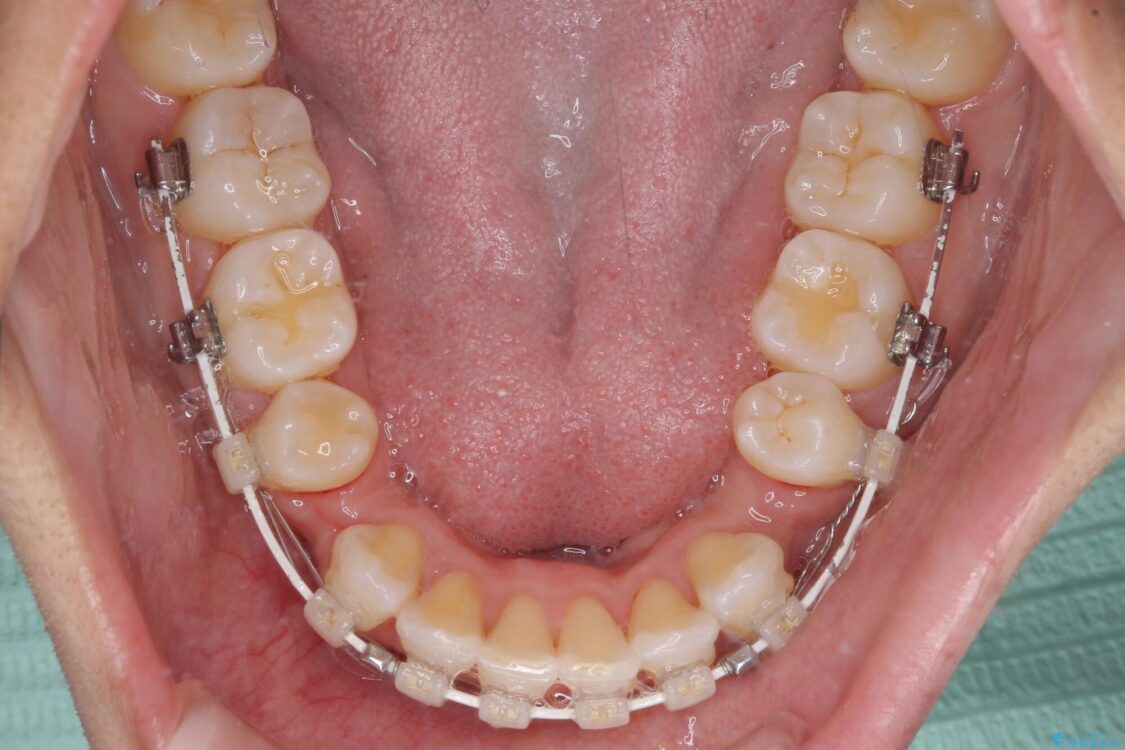

治療途中

• 抜歯矯正で唇を閉じやすく 目立たないワイヤー装置 治療途中画像